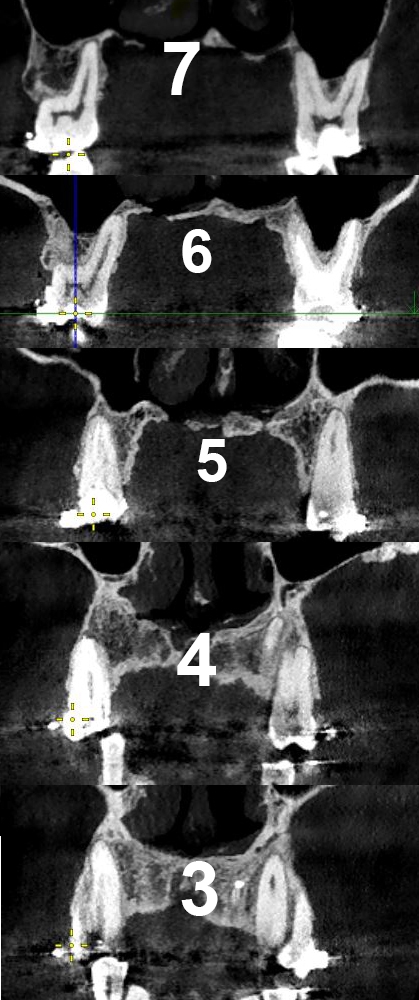

image 206Кб, 1100x564

1100x564

image 296Кб, 1100x746